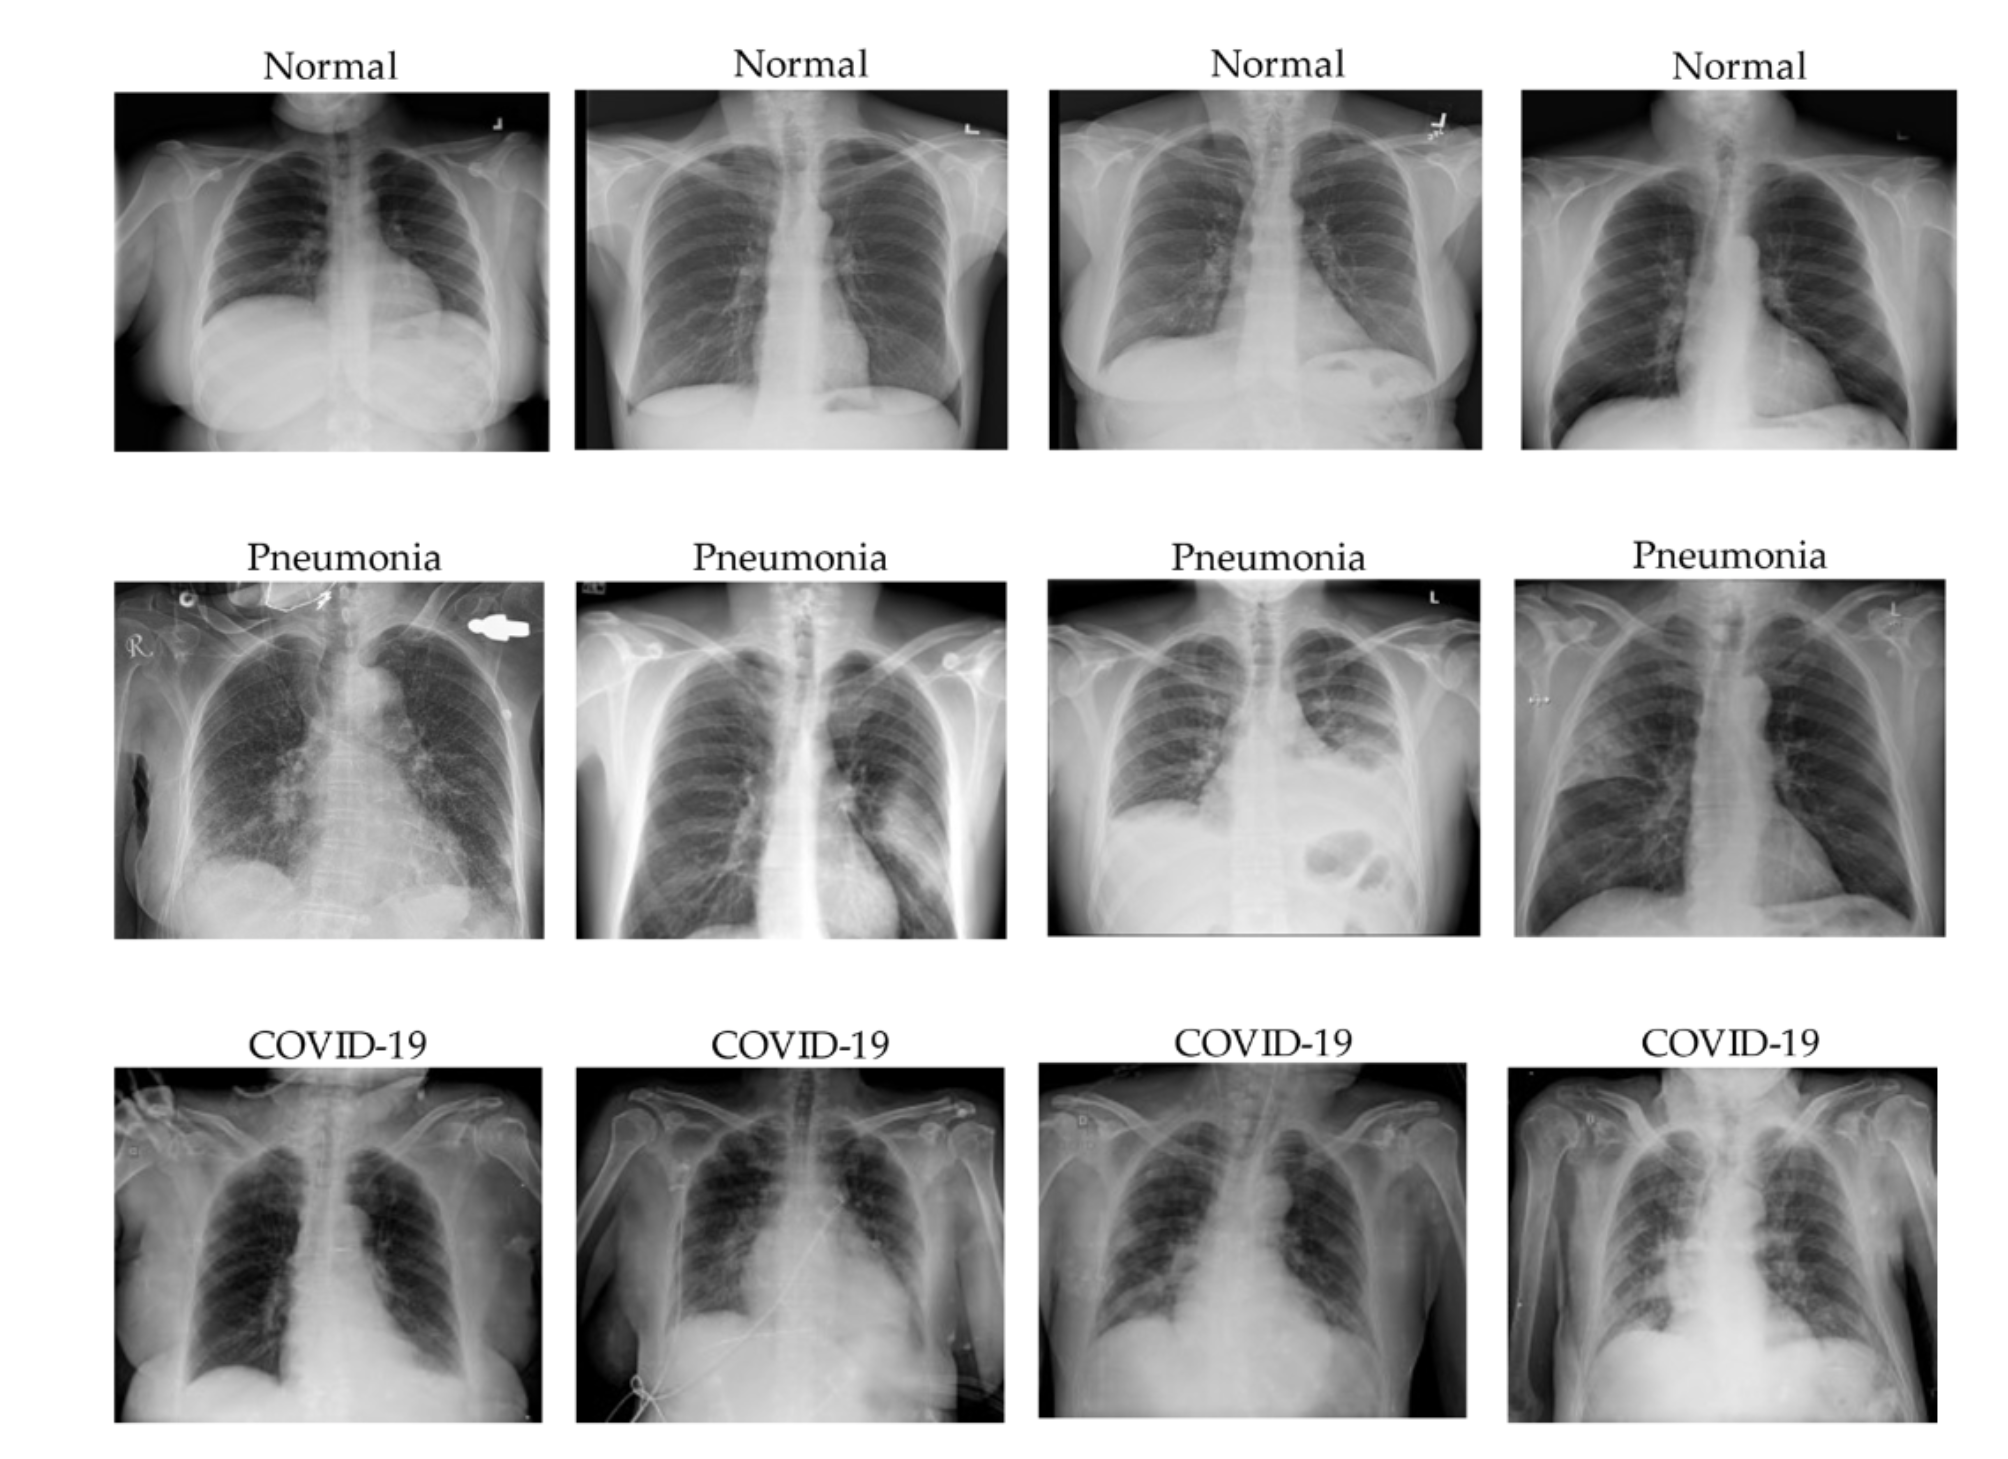

Source: Le Dinh, T., Lee, S. H., Kwon, S. G., & Kwon, K. R. (2022). COVID-19 Chest X-ray Classification and Severity Assessment Using Convolutional and Transformer Neural Networks. Applied Sciences, 12(10), 4861.

Image data